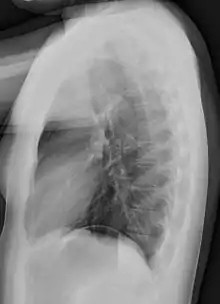

Lateral views of the chest are obtained in a similar fashion as the posteroanterior views, except in the lateral view, the patient stands with both arms raised and the left side of the chest pressed against a flat surface.

Required projections can vary by country and hospital, although an erect posteroanterior (PA) projection is typically the first preference. If this is not possible, then an anteroposterior view will be taken. Further imaging depends on local protocols which is dependent on the hospital protocols, the availability of other imaging modalities and the preference of the image interpreter. In the UK, the standard chest radiography protocol is to take an erect posteroanterior view only and a lateral one only on request by a radiologist.[5] In the US, chest radiography includes a PA and Lateral with the patient standing or sitting up. Special projections include an AP in cases where the image needs to be obtained stat and with a portable device, particularly when a patient cannot be safely positioned upright. Lateral decubitus may be used for visualization of air-fluid levels if an upright image cannot be obtained. Anteroposterior (AP) Axial Lordotic projects the clavicles above the lung fields, allowing better visualization of the apices (which is extremely useful when looking for evidence of primary tuberculosis).